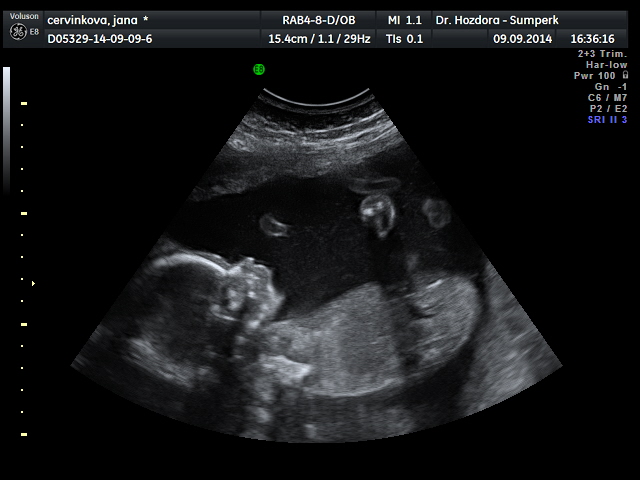

Děvčata,po dnešním ultrazvuku zvyšuju skore holčiček na 13:12. Bude to Marie Jana

Jsem tak happy.